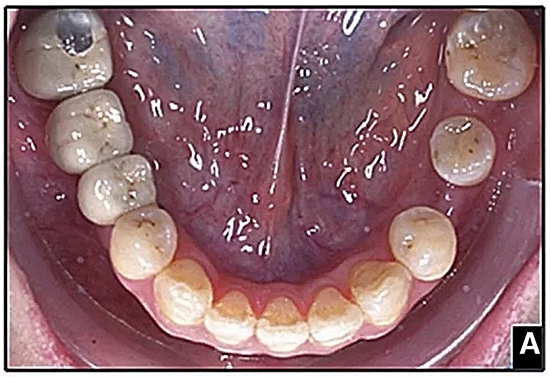

經(jīng)過(guò)32個(gè)月的活動(dòng)治療后,上下牙弓排齊良好,下頜第一磨牙區(qū)的雙側(cè)牙間隙可用于種植(圖12,A和13,A)。

圖15.A,去除固定裝置一個(gè)月后,下頜左側(cè)第二前磨牙復(fù)發(fā),移動(dòng)到種植體愈合的部位; B,B-0表示開(kāi)始再治療,通過(guò)鏈圈和推簧的矯正復(fù)發(fā); C,B-9是治療結(jié)束后3個(gè)月回訪(fǎng)時(shí)下頜弓的咬合面觀(guān),這是再治療階段的9個(gè)月。下頜左側(cè)第二前磨牙和第三磨牙的頰面粘合一個(gè)固定保持器,以防止復(fù)發(fā)。